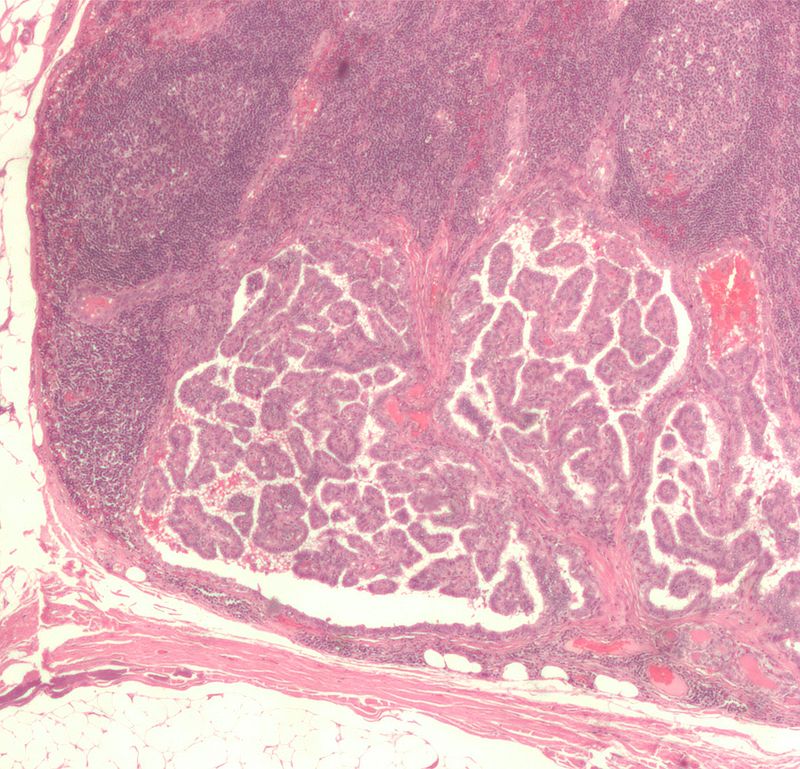

Follicular thyroid carcinoma (FTC) is the malignant proliferation of thyroid follicles with invasion through the capsule.

Follicular thyroid carcinoma invades the capsule.

The distinction between a follicular adenoma and a follicular carcinoma cannot be made by fine needle aspiration (FNA) because FNA only looks at the cells and not the entire capsule under a microscope.